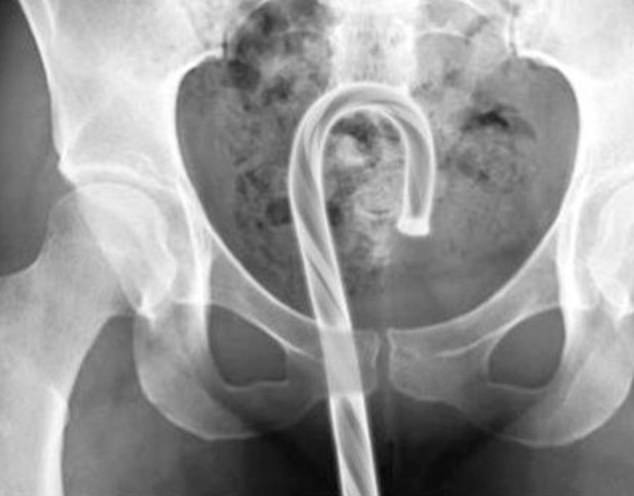

3. Ένα ζαχαρωτό…